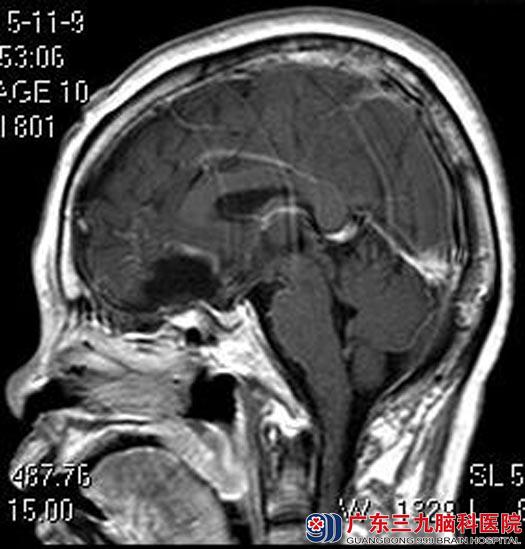

综合神经外科鲁明主任主刀,在全麻下行蝶骨脊脑膜瘤切除术+蝶骨平台增生磨除+前颅底重建+左侧颈内动脉海绵窦段小动脉瘤包裹术。术中显微镜下见肿瘤呈灰白色,予分块全切除;见颈内动脉海绵窦段一小突起动脉瘤,直径约1.5mm,考虑夹闭不能完成,取肌肉包裹动脉瘤,手术很顺利。术后吴奶奶的嗅觉较前恢复,无脑脊液漏等术后并发症。术后病理结果:过渡型脑膜瘤(WHO I级)。